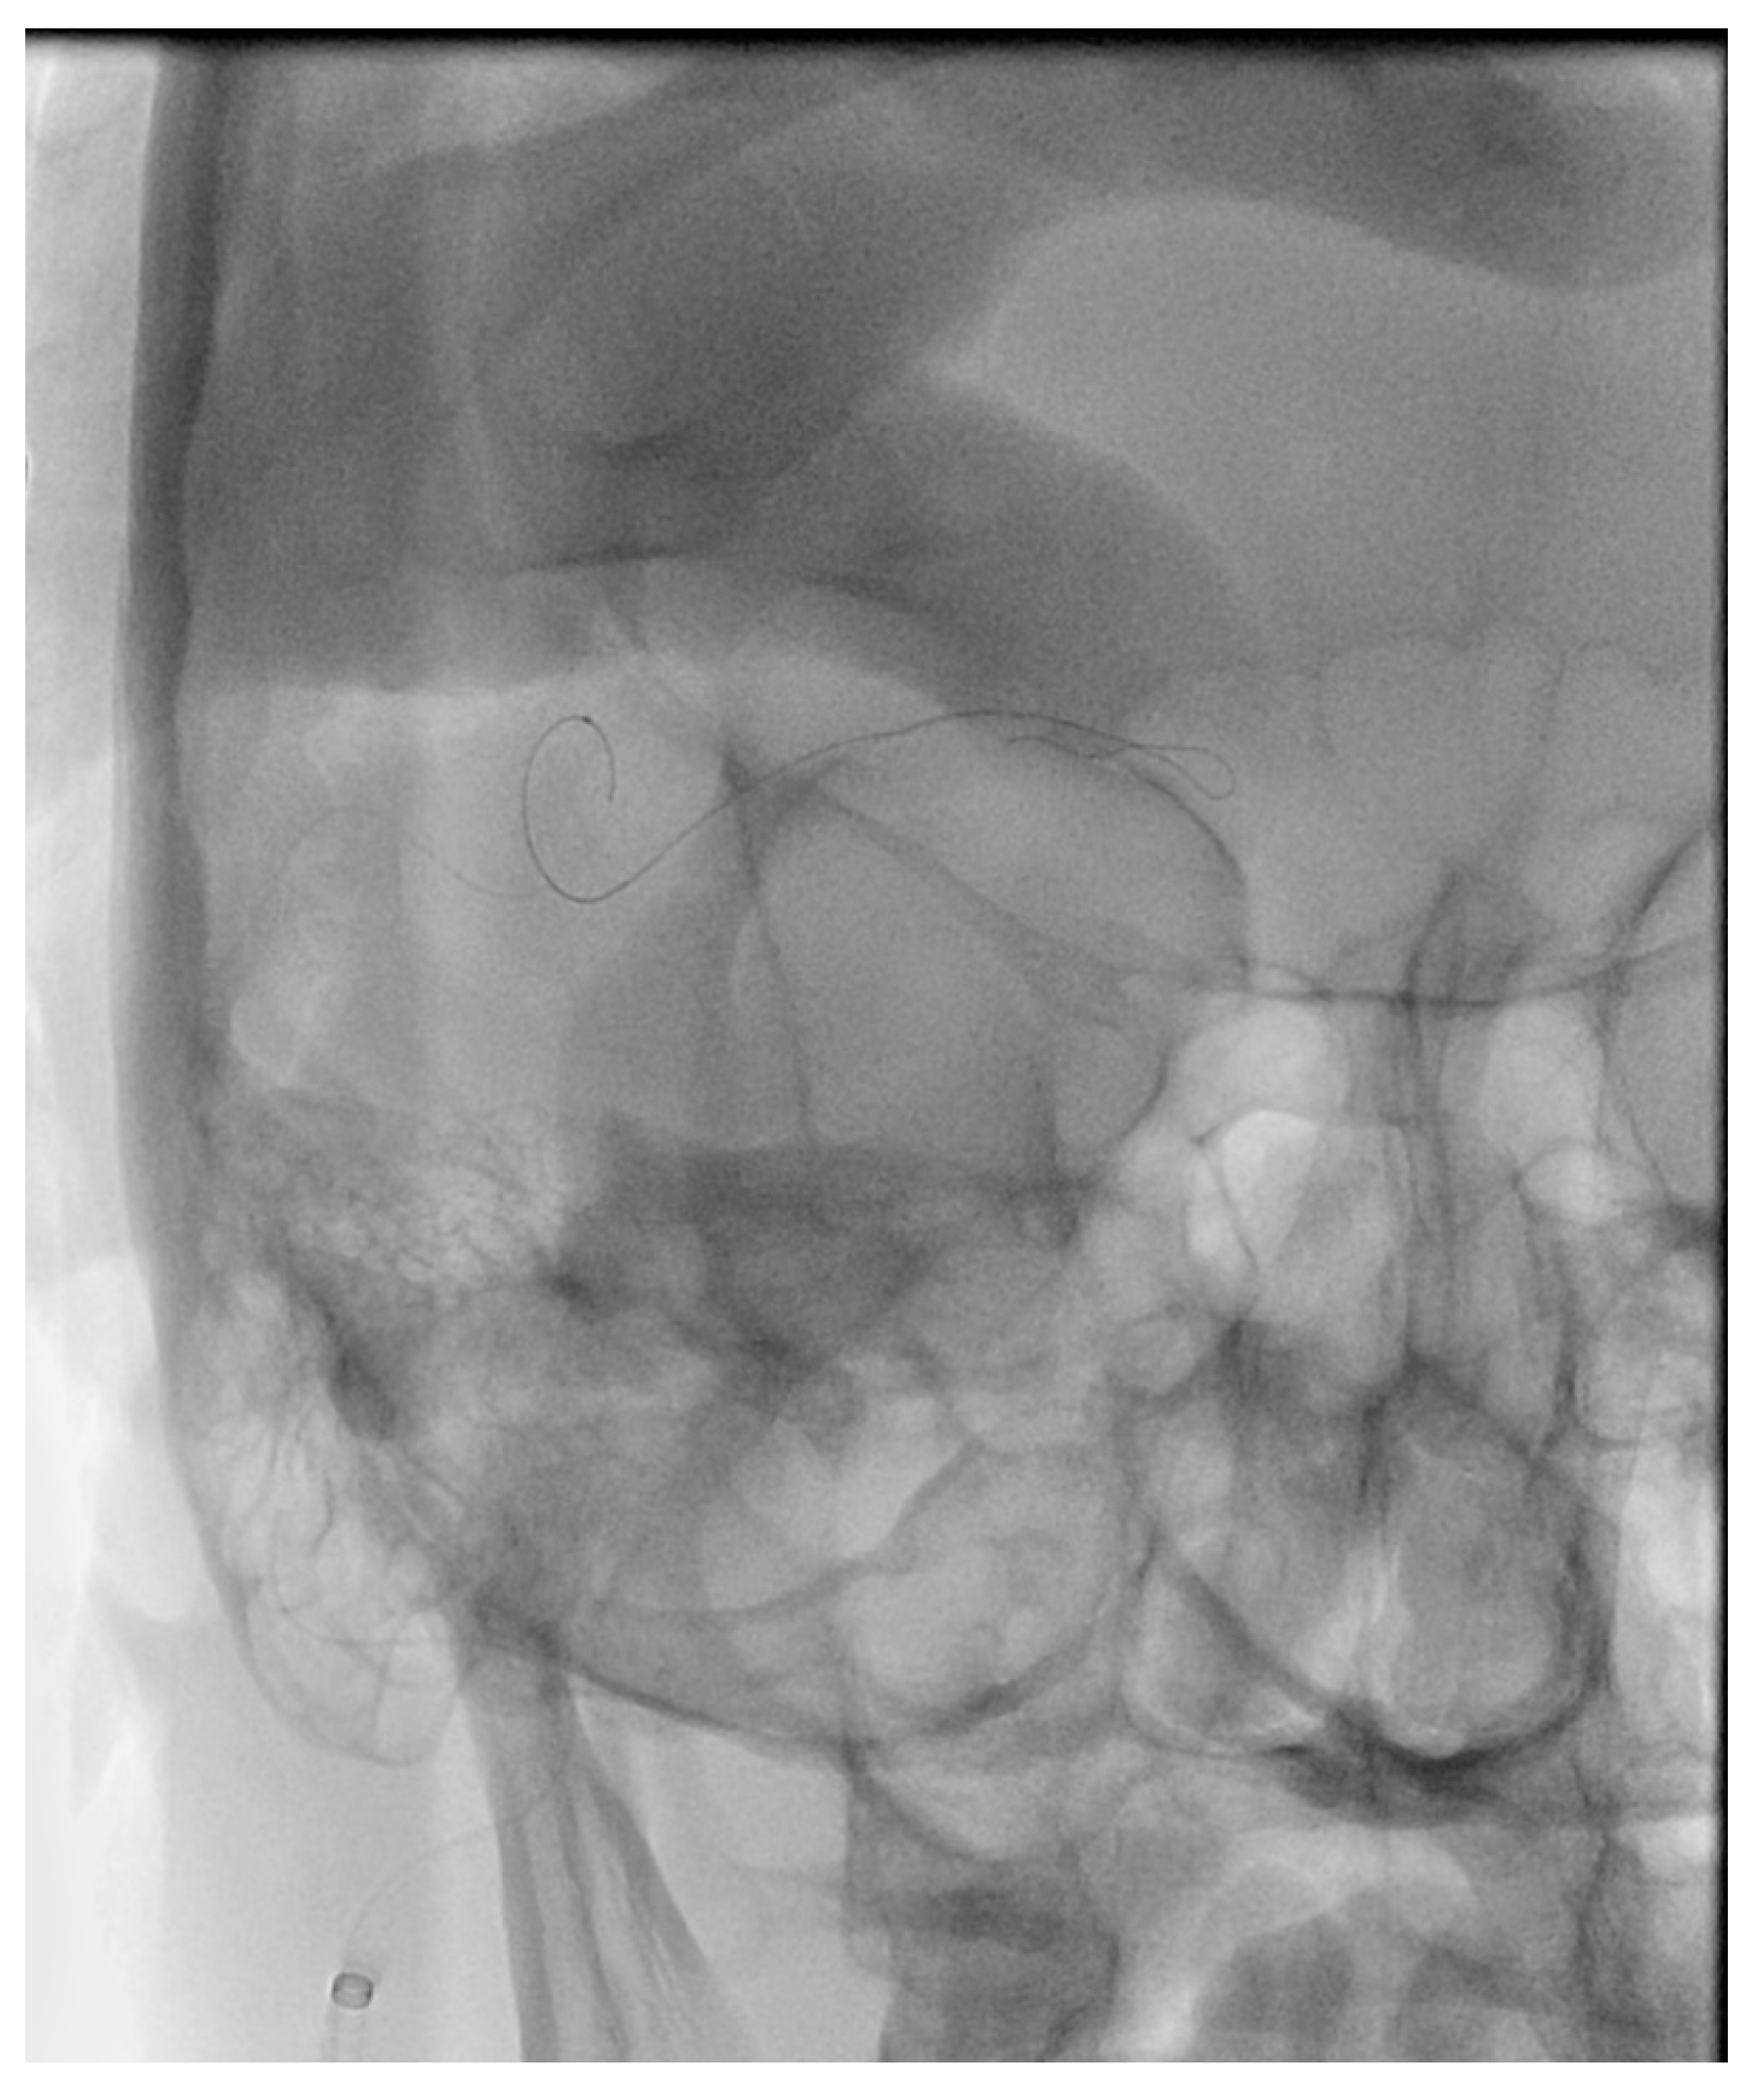

Figure 6. Demonstrates access of the left cavernous sinus (X) through an intercavernous approach (arrows).

Figure 7. Demonstrates percutaneous transorbital puncture of the cavernous sinus (X) via the inferior ophthalmic vein (arrow).